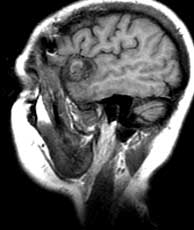

T1 sagittals pre-gad

Findings:

Mixed signal mass (a) in the left Sylvian fissure with surrounding low signal encephalomalacia.